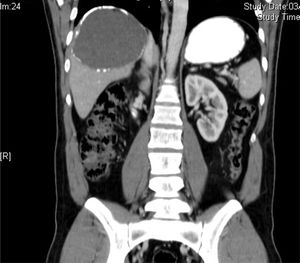

Completamos el estudio con la radiografía de tórax, donde no se aprecian lesiones, y con la tomografía computarizada (TC) abdominal, donde se confirma la existencia de 2 quistes hidatídicos (fig. 2), sin que se observe lesión en el esqueleto axial.